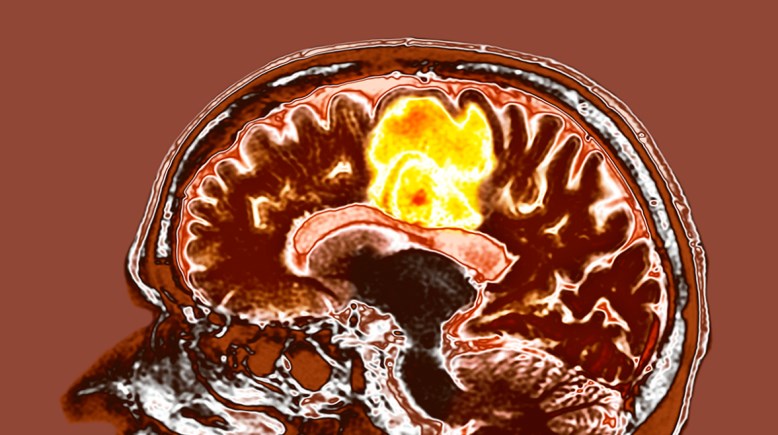

مكملات غذائية تعالج أورام الورم الأرومي

مكملات غذائية شائعة تظهر تأثيرًا محتملًا ضد أورام الدماغ.. تعرف عليها